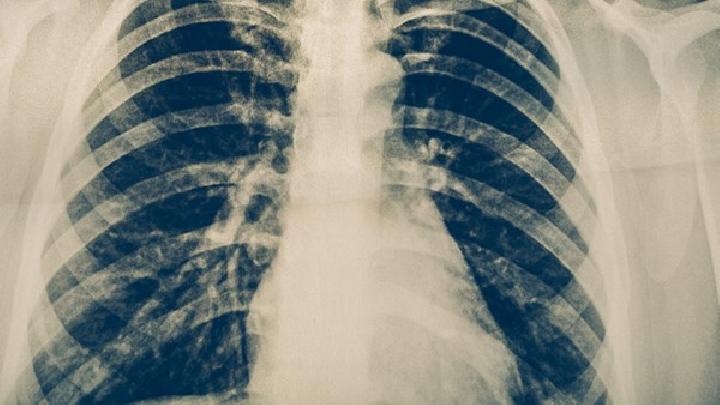

(四)X线路检查 由于急性泌尿道感染本身容易产生膀胱输尿管回流,感染消除后应进行4次静脉或逆行肾盂造影~8周后,急性肾盂肾炎和无并发症的复发性泌尿道感染不提倡常规肾盂造影。对于慢性或长期无法治愈的患者,可根据需要分别进行尿路平片、静脉肾盂造影、逆行肾盂造影、排尿时膀胱输尿管造影,检查是否有梗阻、结石、输静管狭窄或压迫、肾下垂、泌尿系统先天性畸形、膀光输管回流等。此外,我们还可以了解肾盂、肾盏的形成和功能,并与肾结核、肾肿瘤等进行识别。慢性肾盂肾炎的肾盂轻微扩张或杵核,可能有疤痕畸形。肾功能不全时,静脉快速滴入2倍或3倍桌碘造影剂,多次摄影可使造影令人满意。肾血管造影可表明慢性肾盂肾炎的血小管有不同程度的扭曲,必要时可作为肾CT扫描或核磁共振扫描扫描或核磁共振扫描。